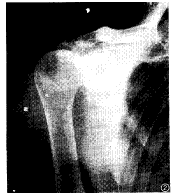

筋腱、滑囊和韌帶鈣化CPPD晶體沉著病患者,可能見有筋腱和韌帶鈣化,常見的部位是跟腱、三頭肌、四頭肌和棘上筋腱以及肩峰下滑囊;有時還可見於髕骨上滑囊。筋腱的鈣化薄而呈線形,可由骨的邊緣延伸至相當遠的距離。合併感染的滑囊鈣化,常見於尺骨鷹嘴處。肩部的肌腱、滑囊鈣化,有時可見於肩袖撕裂傷。